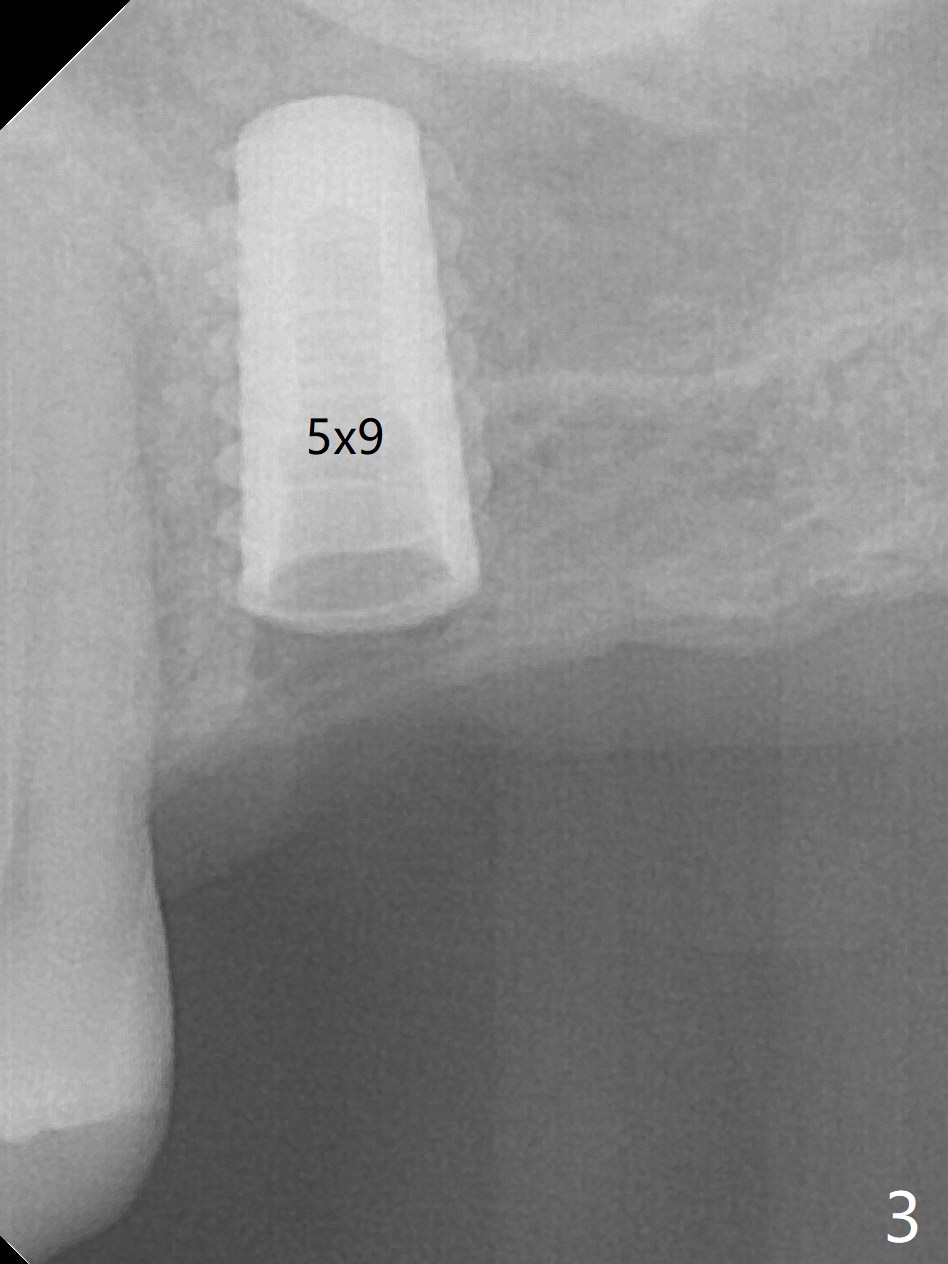

The long 4.8 mm Magic Drill (MD) is used as a tissue punch at the site of #14. After use of a curette to remove the tissue, the MD is used for osteotomy. In fact the osteotomy is mesial with an increase in the osteotomy depth. Magic Lifter, Magic Expander (3 mm) and Magic Drill (3.8 mm) are used to finish sinus lift. Following placement of PRF and Vanilla Graft, a 4.5x11 mm dummy implant is placed (Fig.1,2). The osteotomy seems to be mesial. After use of Lindamann bur distally and 2nd round of PRF membrane and Graft, a 5x9 mm implant is placed > 50 Ncm (Fig.3,4). The final implant appears to remain mesially radiographically. Retrospectively, 1.6 mm pilot drill should have been used with insertion of guide pin after tissue punch. Change in osteotomy position would have been much easier at the early stage. The patient returns for impression 3 months postop; There appears to be space mesial to the implant (Fig.5). The permanent crown will be cemented 2-3 months later. No screw loosens probably related to mesial placement of the implant.